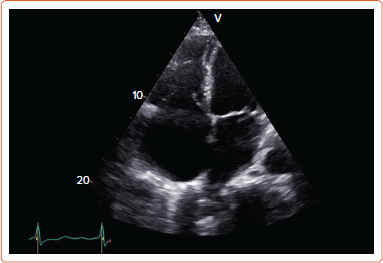

Abstract Image